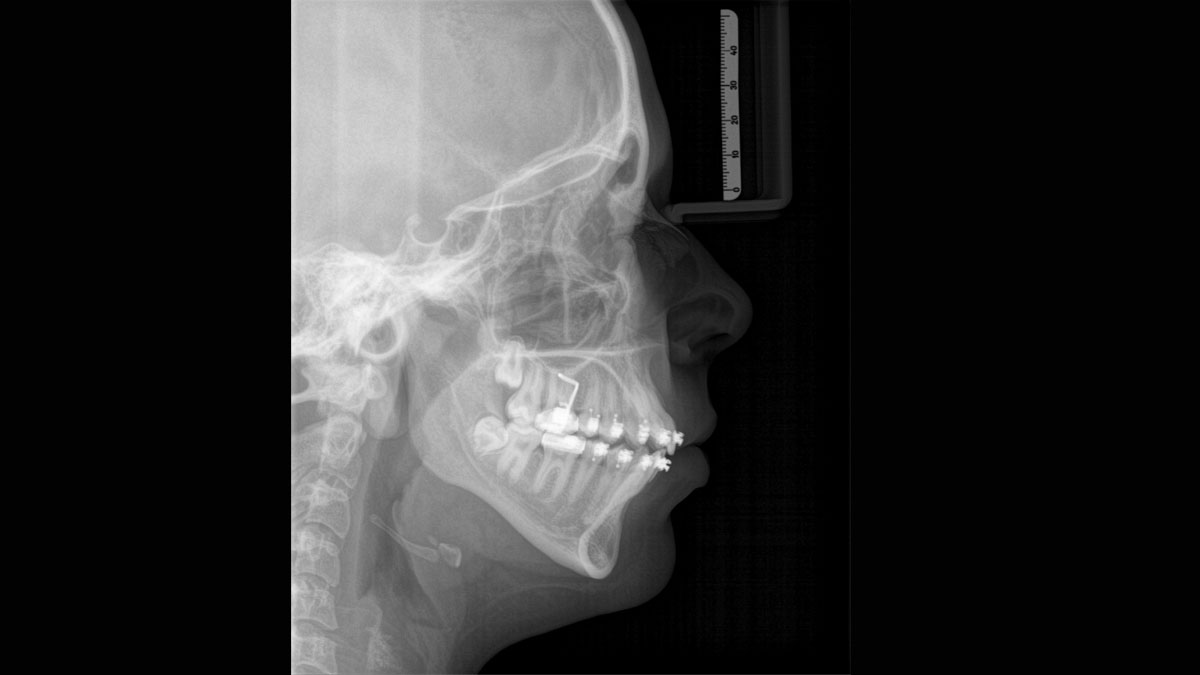

Para obtener imágenes panorámicas excepcionales con alta nitidez. Puede elegir un brazo cefalométrico derecho o izquierdo opcional, que puede reacondicionarse en cualquier momento

Axeos, el sistema especializado 2D/3D con un gran volumen y alta calidad de imagen para clínicas con una amplia oferta de tratamientos. Desarrollado junto a dentistas y clínicos, Axeos ofrece la gama más completa de funciones de todos los equipos de radiología extraoral de Dentsply Sirona. Además de una excelente calidad de imagen y tamaños de volumen 3D personalizados, el equipo de radiología dental está completamente optimizado para una mayor comodidad del paciente. Axeos no solo proporciona calidad en rendimiento y comodidad, sino también con su galardonado diseño gracias al gabinete integrado para el almacenamiento de posicionadores de mordida y la luz ambiental.